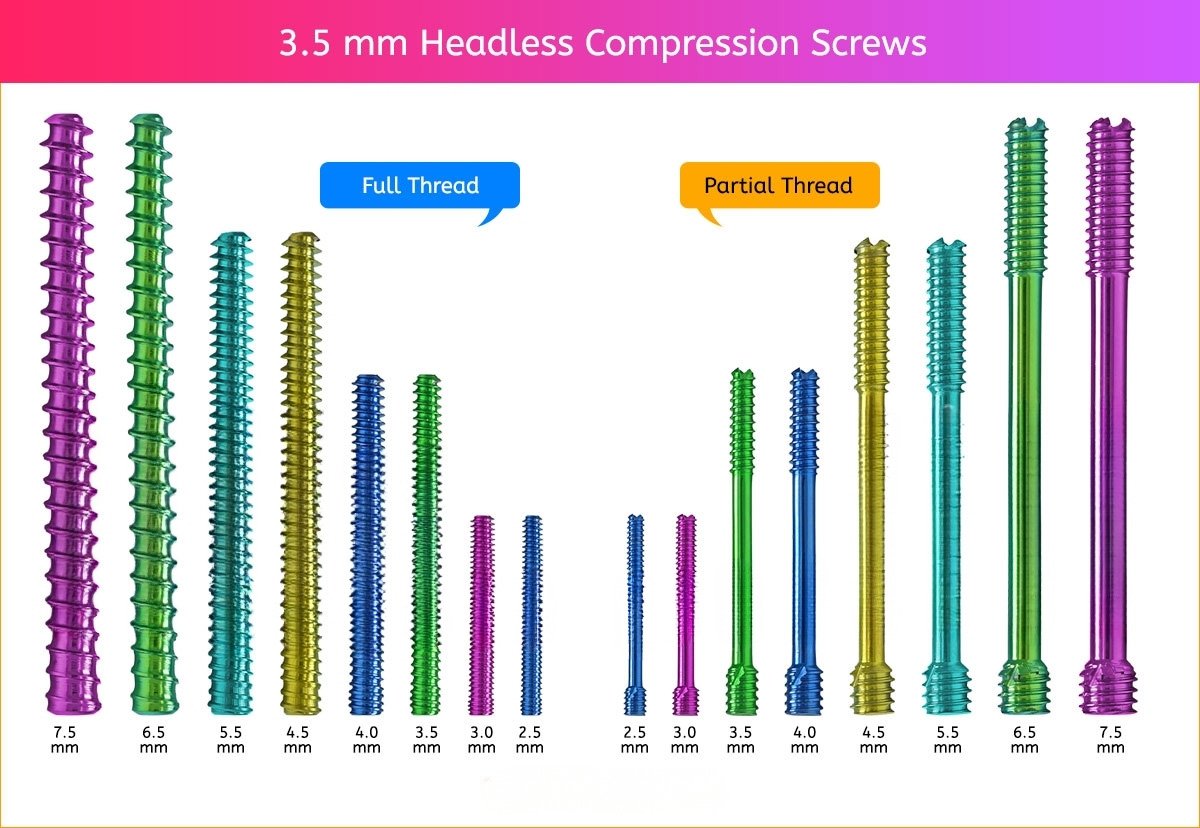

3.5 mm Headless Compression Screw

3.5 mm Screws Length

8mm, 10mm, 12mm, 14mm, 16mm, 18mm, 20mm, 22mm, 24mm, 26mm, 28mm, 30mm, 32mm, 34mm, 36mm, 38mm, 40mm, 42mm, 44mm, 46mm, 48mm, 50mm, 55mm, 60mm, 65mm, 70mm, 75mm and 80mm.